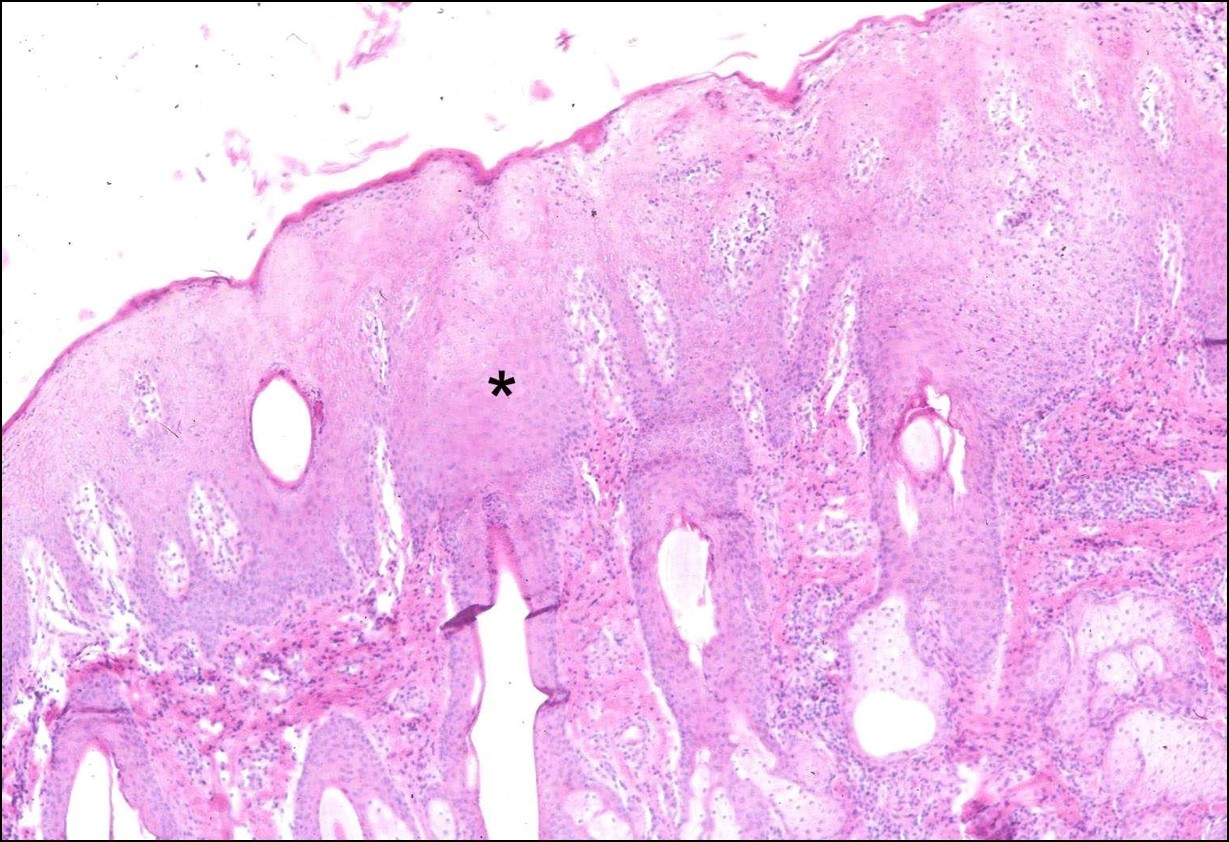

What change is seen here and is it acute or chronic?

Acanthosis, chronic